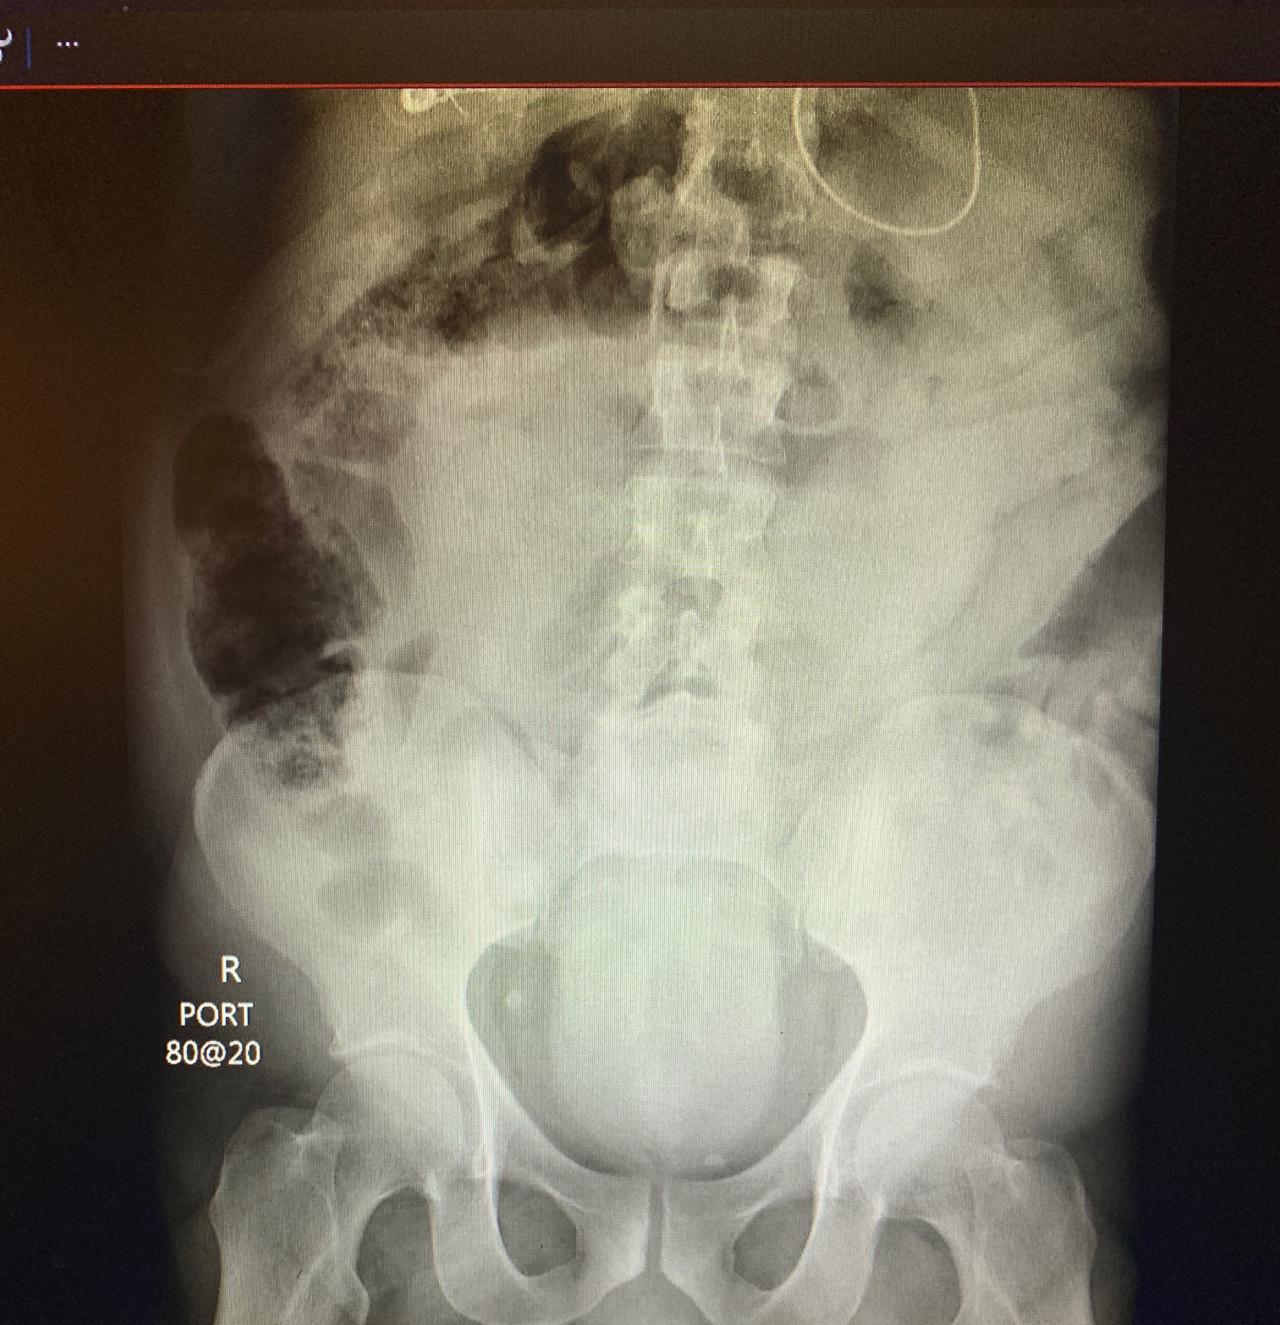

俄羅斯網友在社群網站《VK》分享照片,一名病患的肛門內卡了一隻手臂模型,由於他自己無法取出,只好到醫院找醫生幫忙,動手術後才順利拿出來。X光照清楚可見,整隻模型手臂卡在肚子中,其他照片更可以看到,取出的黑色的右手模型,無論是外型或大小,都與一個成年人的手臂相同無異,想不到竟有人可以將其塞進肛門,就連看慣病患將各種奇物塞進肛門的醫生,在將手臂模型取出後也嚇傻,不可置信。

▼手臂模型卡在肛門。(圖/翻攝自《VK》)